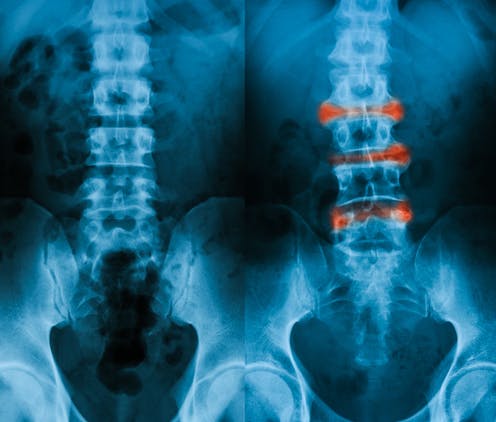

Ankylosing spondylitis (AS) is the second most common type of inflammatory arthritis, often affecting teenagers and young adults. Symptoms of AS can include back pain, stiffness, joint inflammation (arthritis), inflammation where tendons attach to bones (enthesitis), and fatigue. Over time, these symptoms can lead to spinal fusion, which significantly affects quality of life, particularly in young people.

Unfortunately, diagnosing AS can be a lengthy process, taking up to ten years from the onset of symptoms and usually requiring X-rays. The slow progression of the condition, coupled with the lack of a definitive test, contributes to these delays.